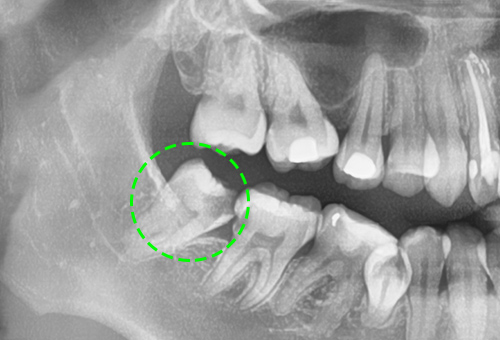

• 기울어진 사랑니

사랑니 바로 앞 어금니를 간섭해, 충치가 발생할 확률이 매우 높고 이로 인해 치열이 불규칙해 질 수 있습니다.

• 누워서 가로로 자란 사랑니

주변치아의 충치와 염증을 유발하기 쉽고, 턱뼈에 압력을 가해 지속적인 통증을 유발하거나,

턱뼈가 약해질 수 있습니다.